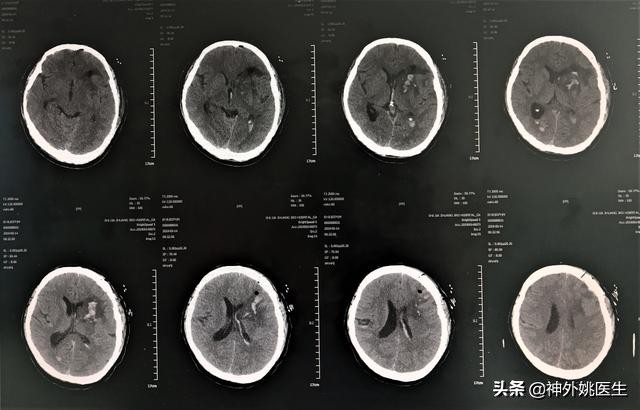

2、头CT复查。(图10)

图10 血肿基本清除。